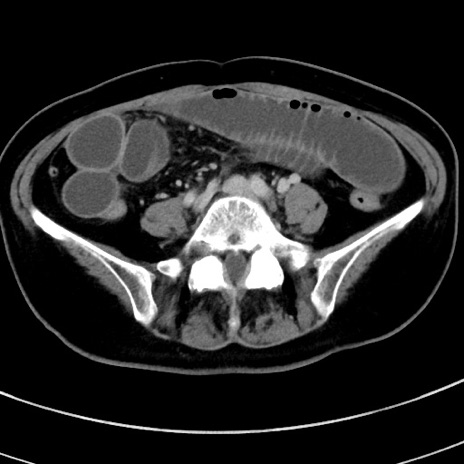

症例9(横断像)

【症例】 60歳代女性

【主訴】むかつき、みぞおちの痛み

【現病歴】3日前よりむかつきがあり、食事がとれない。

【既往歴】糖尿病

【身体所見】発熱なし、心窩部圧痛軽度あるも、腹膜刺激症状なし。

【データ】WBC 7400、CRP 1.92